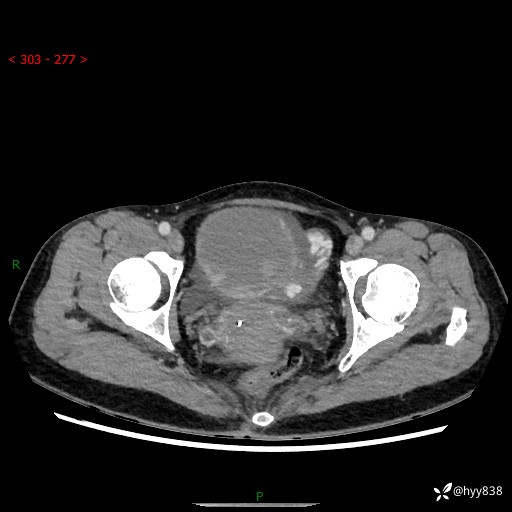

【患者信息】:女,50岁

【主诉】:外院超声发现腹盆肿块,为进一步诊治来我院,门诊已“盆腔肿块”收入院。

腹盆CT平扫+增强

【临床诊断】:盆腔肿瘤